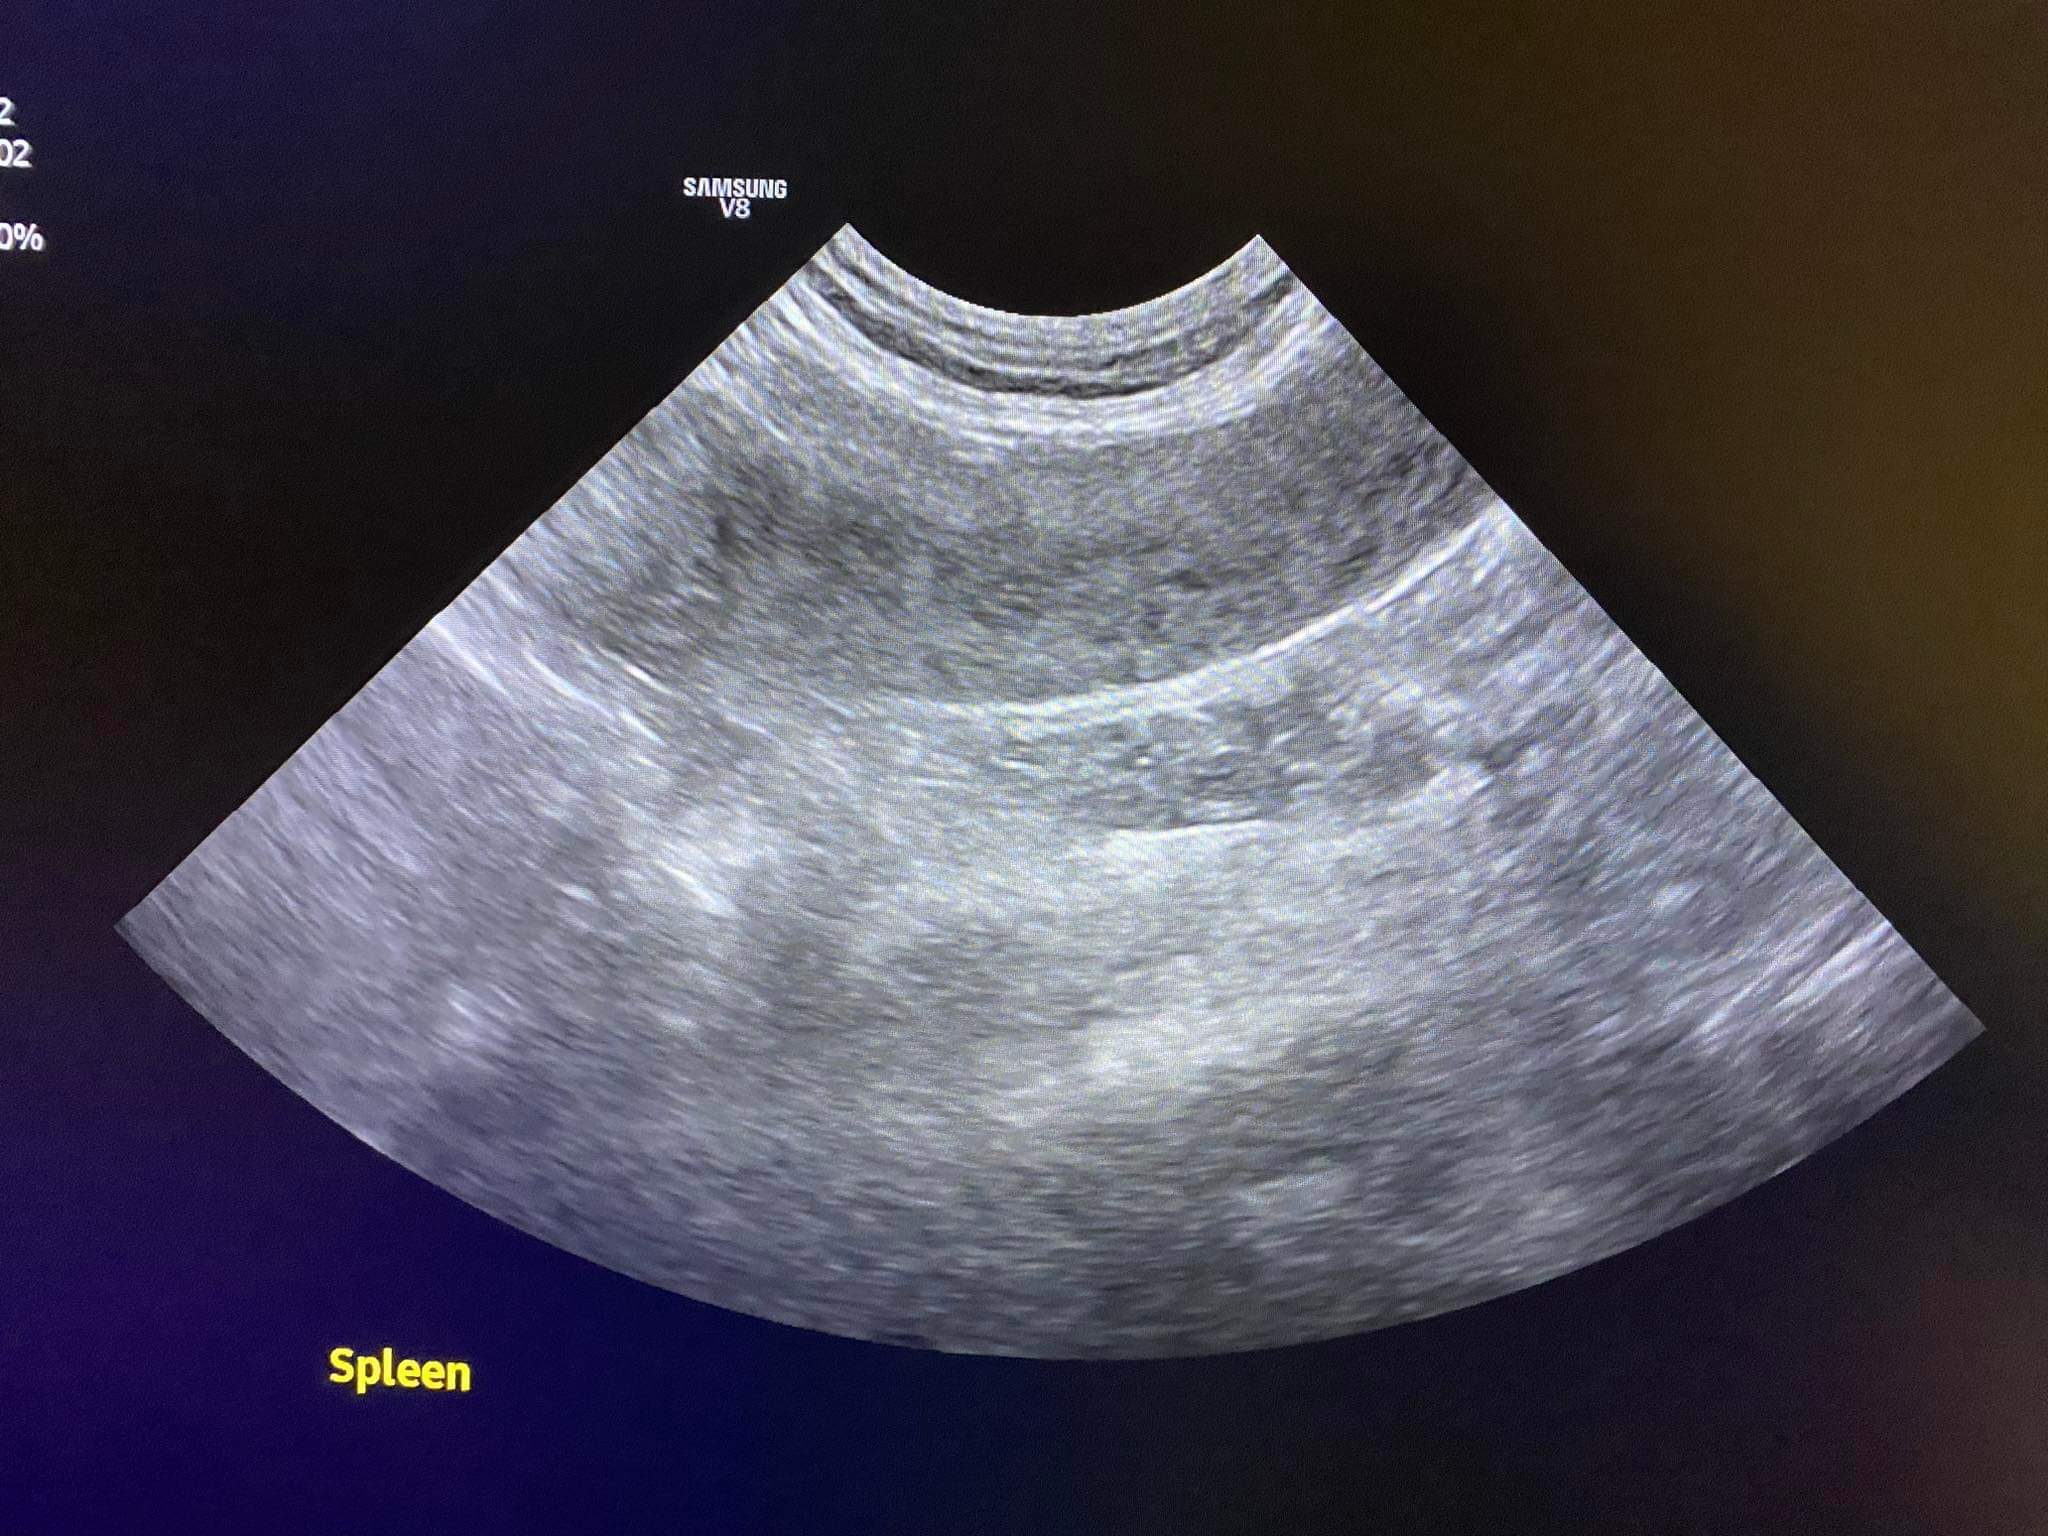

140pm u/s results r out:

Spleen got abnormality

Conclusion: it’s highly likely that it’s dog attack. Trauma to the spleen and bladder and pancreas that cost pancreatitis now.

Dr d:“This whole thing is the heterogenous spleen”